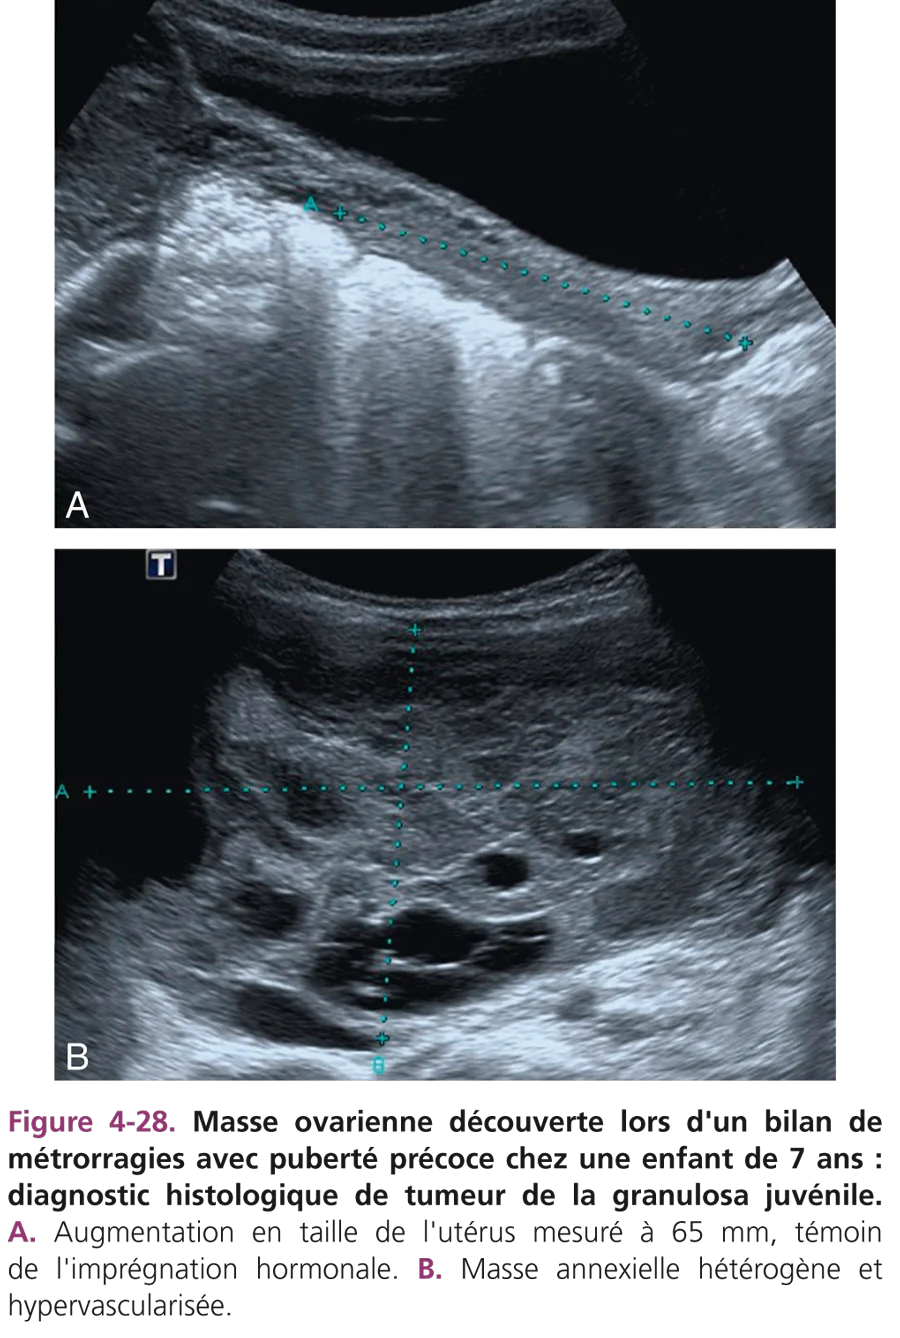

Tumeurs ovariennes

Elles sont rares chez l’enfant et le plus souvent bénignes, représentées essentiellement par des tumeurs germinales. Le tératome mature représente 90 % des tumeurs bénignes. Le tératome mature ou kyste dermoïde est la principale tumeur de l’ovaire chez l’enfant. Il survient principalement entre 6 et 11 ans bien qu’il puisse être observé à tout âge. Environ 10 % de ces tumeurs sont bilatérales. En échographie, la lésion est hétérogène et comporte une partie kystique avec un ou plusieurs nodules muraux échogènes, graisseux et/ou calciques (fig. 4-27). La présence de structure dentaire ou osseuse est très caractéristique. La masse peut contenir un liquide épais, sébacé, échogène. Le scanner ou l’IRM permet d’identifier le contenu calcique et graisseux et de vérifier l’ensemble de la cavité abdominopelvienne (foie, adénopathies, épanchement intrapéritonéal). Le dosage des marqueurs tumoraux est systématiquement effectué (alpha-foetoprotéine et β-hCG). Les tumeurs germinales malignes sont rares et représentent environ 85 % des tumeurs malignes de l’ovaire chez l’enfant. Elles se rencontrent surtout entre 10 et 15 ans. Il s’agit souvent de tumeurs germinales malignes mixtes associant différentes composantes. Les contingents sécrétants sont les tumeurs du sac vitellin (ou tumeurs du sinus endodermique) sécrétant de l’alpha-foetoprotéine et les choriocarcinomes produisant de la β-hCG.